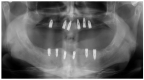

Optimal functional outcomes in oncologic patients with squamous cell carcinoma (SCCA) of the tongue and floor of the mouth require good lingual mobility, adequate facial competence, the cheek suction effect and dental rehabilitation with osseointegrated implants. In this study, twenty-two oncologic patients who had been diagnosed with intraoral SCCA affecting the tongue and the floor of the mouth and who had undergone wide resection of the tumor and immediate reconstruction with an inferiorly pedicled FAMM flap and immediate osseointegrated implants were assessed. Lingual mobility, speech articulation, deglutition, implant success rate, mouth opening, and aesthetic results were evaluated. All patients were staged as T2 and the defect size ranged from 3.7 × 2.1 cm to 6.3 × 4.2 cm. A selective neck dissection was performed in all patients as part of their oncologic treatment, either electively or for node positive disease. Thirteen patients (59%) were diagnosed with node positive disease and underwent adjuvant radiotherapy. A total of 101 osseointegrated implants were placed for prosthetic rehabilitation and 8 implants were lost (7.9%), of which 7 received radiotherapy (87.5%). The implant success rate was 92.1%. Mouth opening was reported as normal in 19 patients (86.3%). Tongue tip elevation was reported as excellent in 19 patients (86.3%) and good in 3 patients (13.6%). Lingual protrusion was referred to as excellent in 15 patients (68.2%) and good in 6 patients (27.2%). Lateral excursion was reported as excellent in 14 patients (63.6%) and good in 7 patients (31.8%). In terms of speech articulation, 20 patients reported normal speech (90.9%). Regarding deglutition, 19 patients (86.3%) reported a regular diet while a soft diet was reported by 3 patients (13.7%). Aesthetic results were referred to as excellent in 17 patients (77.3%). FAMM flaps, immediate implants and fixed prostheses enable the functional rehabilitation of oncologic patients, optimizing aesthetics and functional outcomes even in patients undergoing irradiation, thus returning oncologic patients to an excellent quality of life.